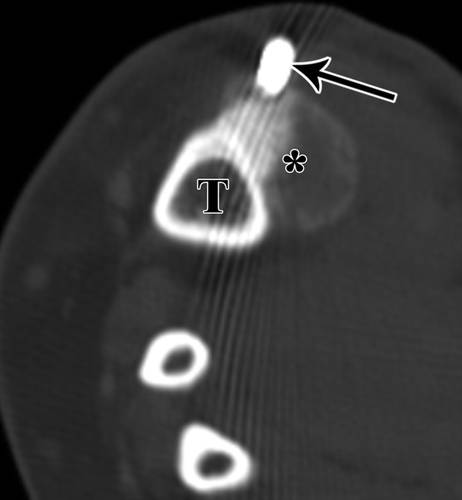

胫骨和腓骨之间的骨间膜是肿瘤扩散的天然屏障。因为前内侧胫骨是皮下的,所以可以避免两个隔间(图11)和12)。

![]()

11 -小腿的插图。

轴位图显示胫骨活检(绿色和箭头)的最佳入口位置,避免肌肉室。T =胫骨,F =腓骨。

12 - 52岁女性内生软骨瘤。